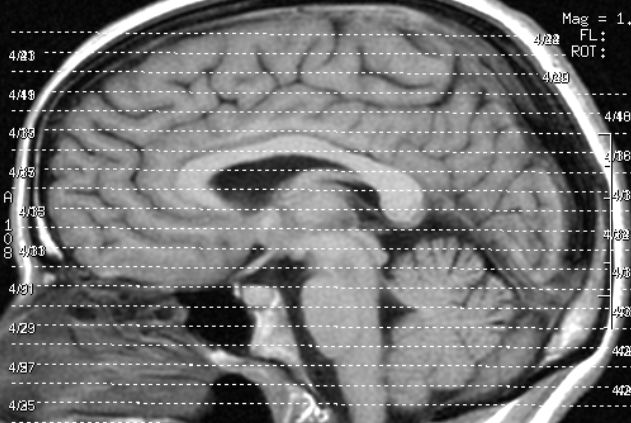

Um herauszufinden, wie sich Videospielen auf das Gehirn auswirkt, ließen die Wissenschaftler Erwachsene über zwei Monate hinweg täglich 30 Minuten das Videospiel „Super Mario 64“ spielen. Eine Kontrollgruppe durfte nicht spielen. Mit Hilfe der Magnetresonanztomographie (MRT) wurde die Struktur des Gehirns vermessen. Im Vergleich zur Kontrollgruppe zeigte sich bei den Videospielprobanden eine Vergrößerung einiger Bereiche der grauen Substanz, in der sich die Zellkörper der Nervenzellen des Gehirns befinden. Die Vergrößerung umfasste den rechten Hippokampus, den präfrontalen Kortex und Teile des Kleinhirns. Diese Hirnareale sind unter anderem für räumliche Orientierung, Gedächtnisbildung, strategisches Denken sowie für die Feinmotorik der Hände von zentraler Bedeutung. Interessanterweise waren diese Veränderungen umso ausgeprägter, je mehr Spaß die Probanden beim Spielen hatten.

„Während vorhergehende Studien veränderte Hirnstrukturen bei Videospielern lediglich vermuten konnten, können wir mit dieser Studie einen direkten Zusammenhang zwischen dem Spielen und einem Volumenzuwachs nachweisen. Das belegt, dass sich bestimmte Hirnregionen durch Videospielen gezielt trainieren lassen“, sagt Studienleiterin Simone Kühn, Wissenschaftlerin am Forschungsbereich Entwicklungspsychologie des Max-Planck-Instituts für Bildungsforschung. Deshalb vermuten die Forscher, dass sich Videospiele für die Therapie von Erkrankungen eignen könnten, bei denen die entsprechenden Hirnregionen verändert sind. Das ist zum Beispiel bei psychischen Störungen wie der Schizophrenie, der posttraumatischen Belastungsstörung oder neurodegenerativen Erkrankungen wie der Alzheimer-Demenz der Fall.